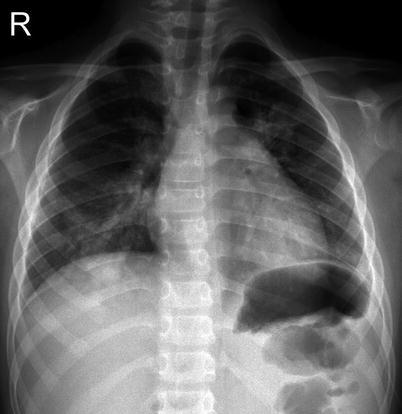

The radiographic findings are nonspecific, have a broad spectrum of appearances, and may present with a pattern intermediate between the classic viral and bacterial pneumonia patterns (Hsieh et al. 2007). Some authors reported that a reticulonodular pattern or nodular opacities are typical radiographic pattern (John et al. 2001), while others stress the occurrence of confluent and patchy consolidation (Reittner et al. 2000) (Fig. 13.15). HRCT findings are thickened bronchovascular bundles, ground-glass attenuation and consolidation, centrilobular nodules, and lobular distribution (Tanaka et al. 1996; Reittner et al. 2000).

Fig. 13.15.

Variable imaging pattern of Mycoplasma pneumonia. Chest x-ray of a 10-year-old boy (a) demonstrates generalized increase interstitial marking with scattered patchy areas of opacity. Another patient diagnosed with Mycoplasma infection demonstrating patchy consolidation on the right middle and lower lobes (b)